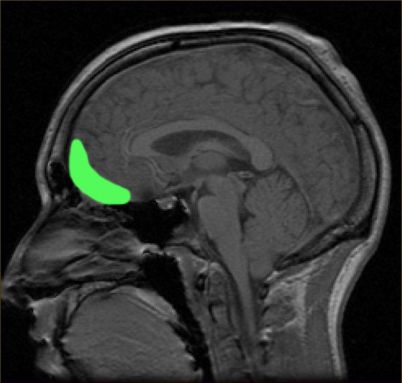

The size and shape of certain brain regions are different in people with eating disorders. Frank led two 2013 studies that illustrate this. Both showed important structural differences in certain brain regions.

Take the orbitofrontal cortex. This brain region sits just between the eyes. It is larger than normal in young people and adults with anorexia nervosa and bulimia nervosa. Study participants who had recovered from anorexia showed this same enlargement.

This may be an important clue: The affected region includes a structure called the gyrus rectus (JY-rus REK-tus). It plays an important role in regulating how much we eat.

Frank and his fellow researchers found that a second structure, the right insula, also was enlarged in patients with anorexia and in people who had recovered from the illness. In patients with bulimia, the left insula was larger than in healthy people.

The left and right insula are tucked deep inside the brain. The insula tell us what taste we just experienced. It then connects with other brain regions to allow us to feel pleasure or dislike about that taste. Now we can make a decision whether we want more of a particular food, says Frank. The insula also integrates how we feel about our body and our sensation of pain.

Whether these altered regions help trigger eating disorders or instead are caused by them remains unknown, Frank says.

But the new studies do show that these illnesses have a strong basis in brain biology, he says. And those biological origins of eating disorders may occur early in brain development.

These data can help “people to understand what these kids and their families are up against,” Frank says. “It’s not ‘just the fear of weight gain’ and ‘just the fear of getting fat,’” he says. “It’s also something clearly biological that makes it really hard for them to go back to normal.”